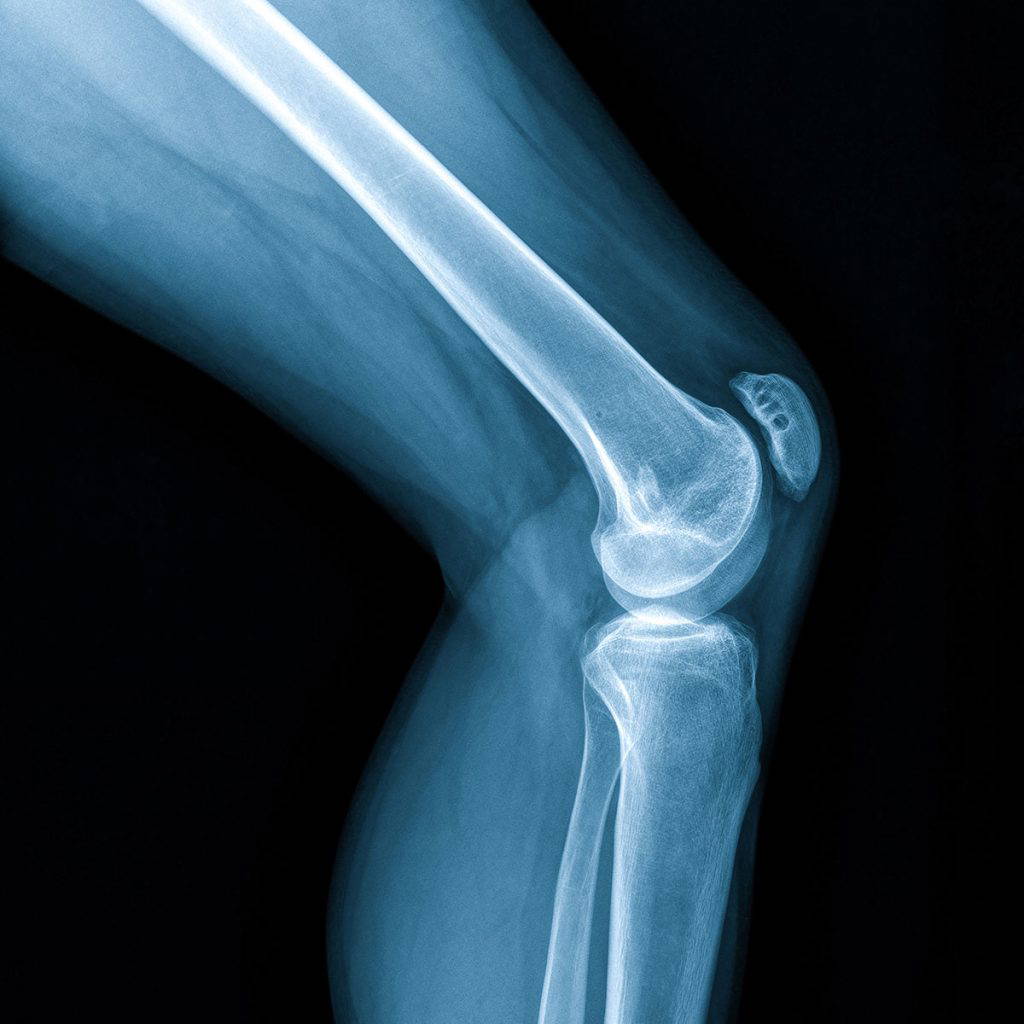

Total or Partial Knee Replacement

A knee replacement involves replacing the worn out areas of your knee with a smooth metal on plastic surface. It is commonly indicated for conditions such as osteoarthritis, rheumatoid arthritis, and post traumatic wear.

A partial knee replacement option is also available for knee conditions affecting only a single compartment.